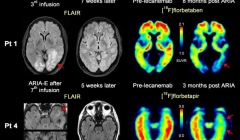

Chiarito il meccanismo che porta all'Alzheimer e come fermarlo

30.08.2017 | Ricerche

Nel cervello delle persone con Alzheimer ci sono depositi anomali di proteine amiloid...